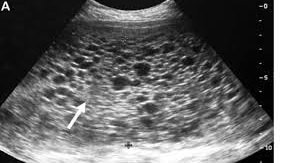

Chẩn đoán hình ảnh :Với siêu âm, có thể chẩn đoán chửa trứng có thể được phát hiện rất sớm và dễ dàng, thường ở thai

Trên siêu âm thấy hình ảnh tuyết rơi hoặc lỗ chỗ như tổ ong, có thể thấy nang hoàng tuyến hai bên, không thấy phôi thai (chửa trứng toàn phần). Trong chửa trứng bán phần thì khó phân biệt hơn với thai lưu, có thể thấy một phần bánh rau bất thường.Thực hiện các xét nghiệm